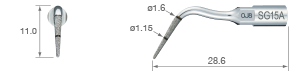

IMPLANT PREPARATION

Contenido

• SG15A, SG15B, SG16A, SG16B

• Soporte para puntas